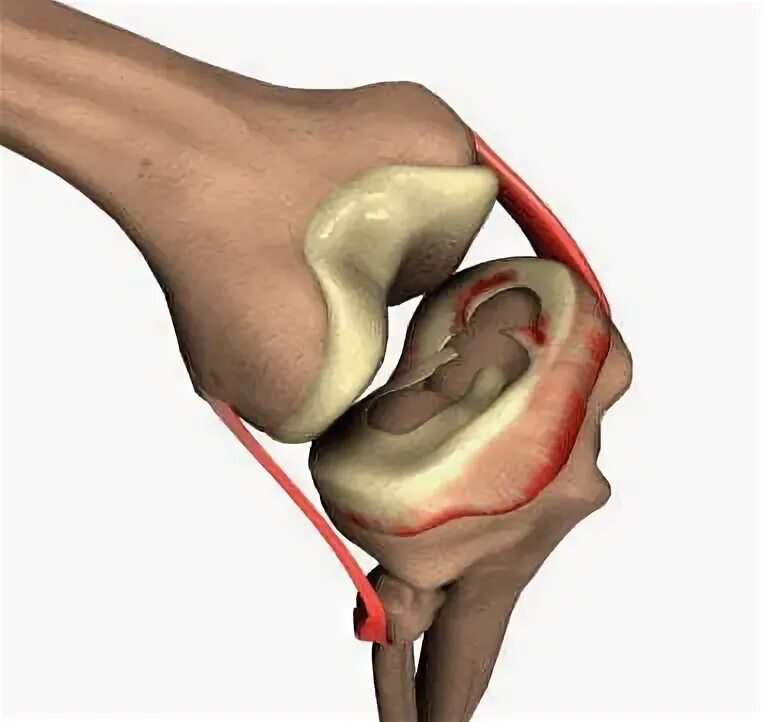

Stoller 3b разрыв